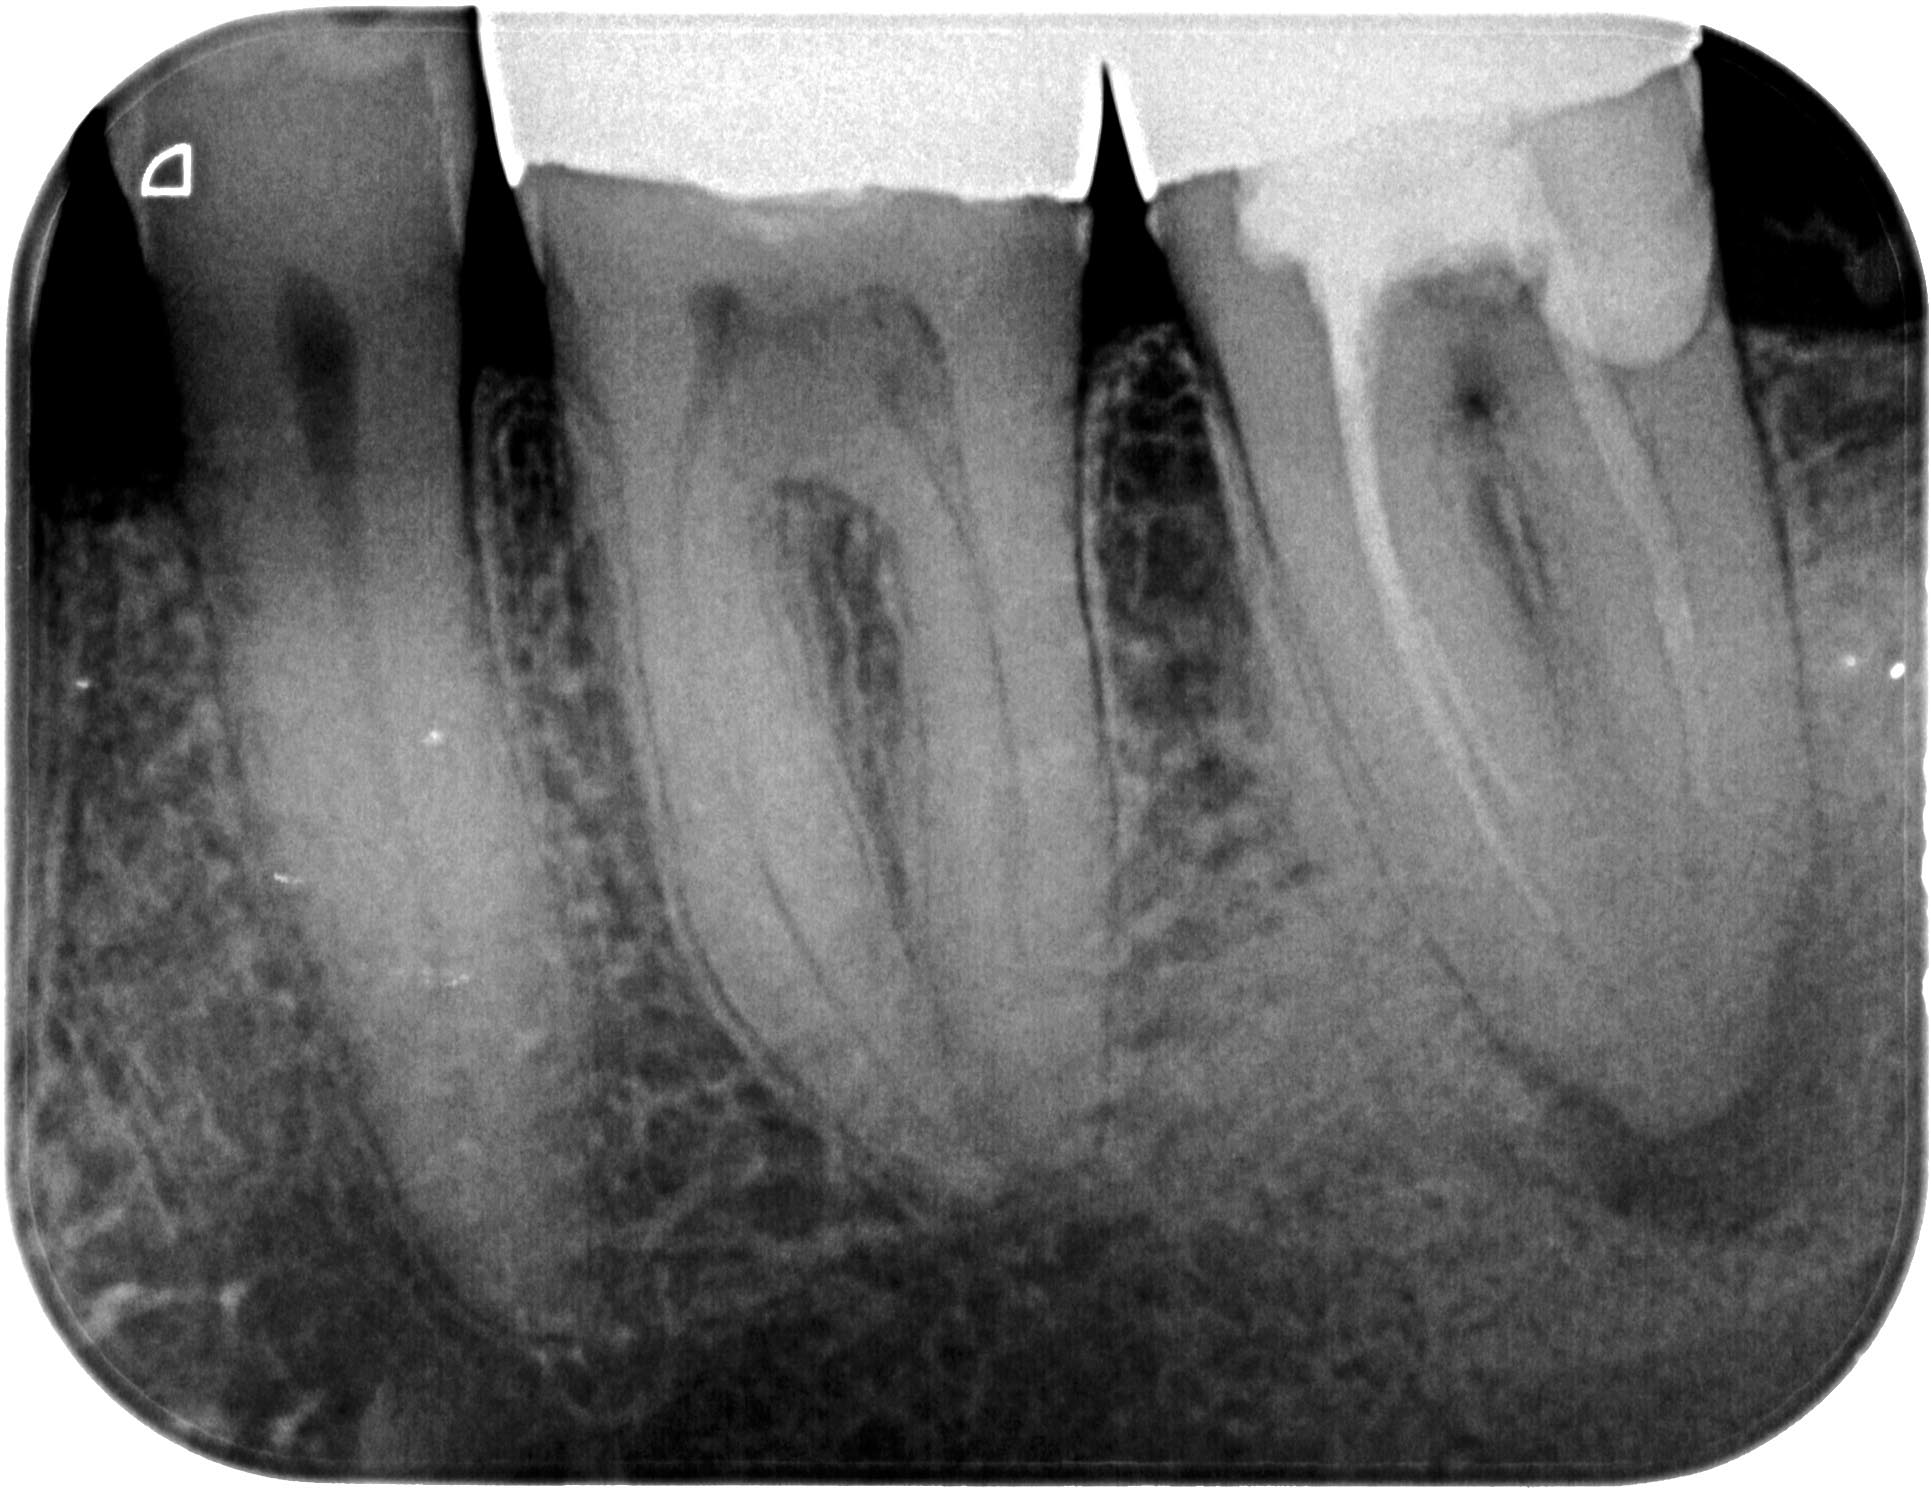

KSKrone6MonatepostWF-1-2 Veröffentlicht 24. September 2015 am 1931 × 1488 in Zuverlässige Endometrie bei Metallkronen – aber auch – Wäre das nicht eine sinnvolle neue Rubrik für WURZELSPITZE ? Zahn 37 vor WF- Revision